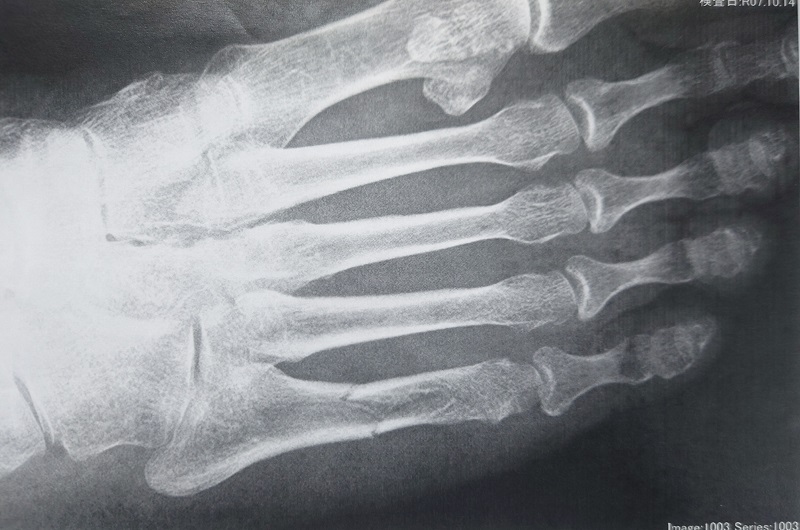

右第5中足骨粉砕骨折(80代女性)の施術一例